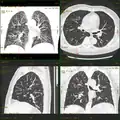

-

Craniale Computertomographie Abgebildet sind Felsenbein und Nasennebenhöhlen. Aufgrund der hohen Auflösung der Aufnahme des verwendeten 64-Zeilen-CTs sind selbst die Gehörknöchelchen erkennbar. -

Koronal reformatierte Darstellung von Abdomen und Becken; gut zu erkennen sind u. a. die Leber und die beiden Nieren. -

Kombination aus multiplanarer Reformatierung und sliding thin slab. Der Bildkursor befindet sich in der Harnblase. Die Originalschichtdicke beträgt 1,25 mm, dargestellt wird in allen Ansichten gemittelt (= average) in 3,7 mm bzw. 3,8 mm Dicke. -

Kombination aus multiplanarer Reformatierung und sliding thin slab. Der Bildkursor befindet sich im rechten Lungenflügel. Die sts-Bildstapel werden in Form von MIP-Darstellungen gezeigt (STS-MIP).[52] Links oben befindet sich eine VR-Darstellung der Lunge; sie zeigt einen Blick auf die koronal an Kursorposition geschnittene Lunge. -

CT-Angiographie; mittels multiplanarer Reformation (hier die sog. curved MPR) sind auch Schnittdarstellungen entlang beliebiger Gefäßverläufe möglich, wodurch die gezeigte Arteriosklerose sehr gut visualisiert werden kann.